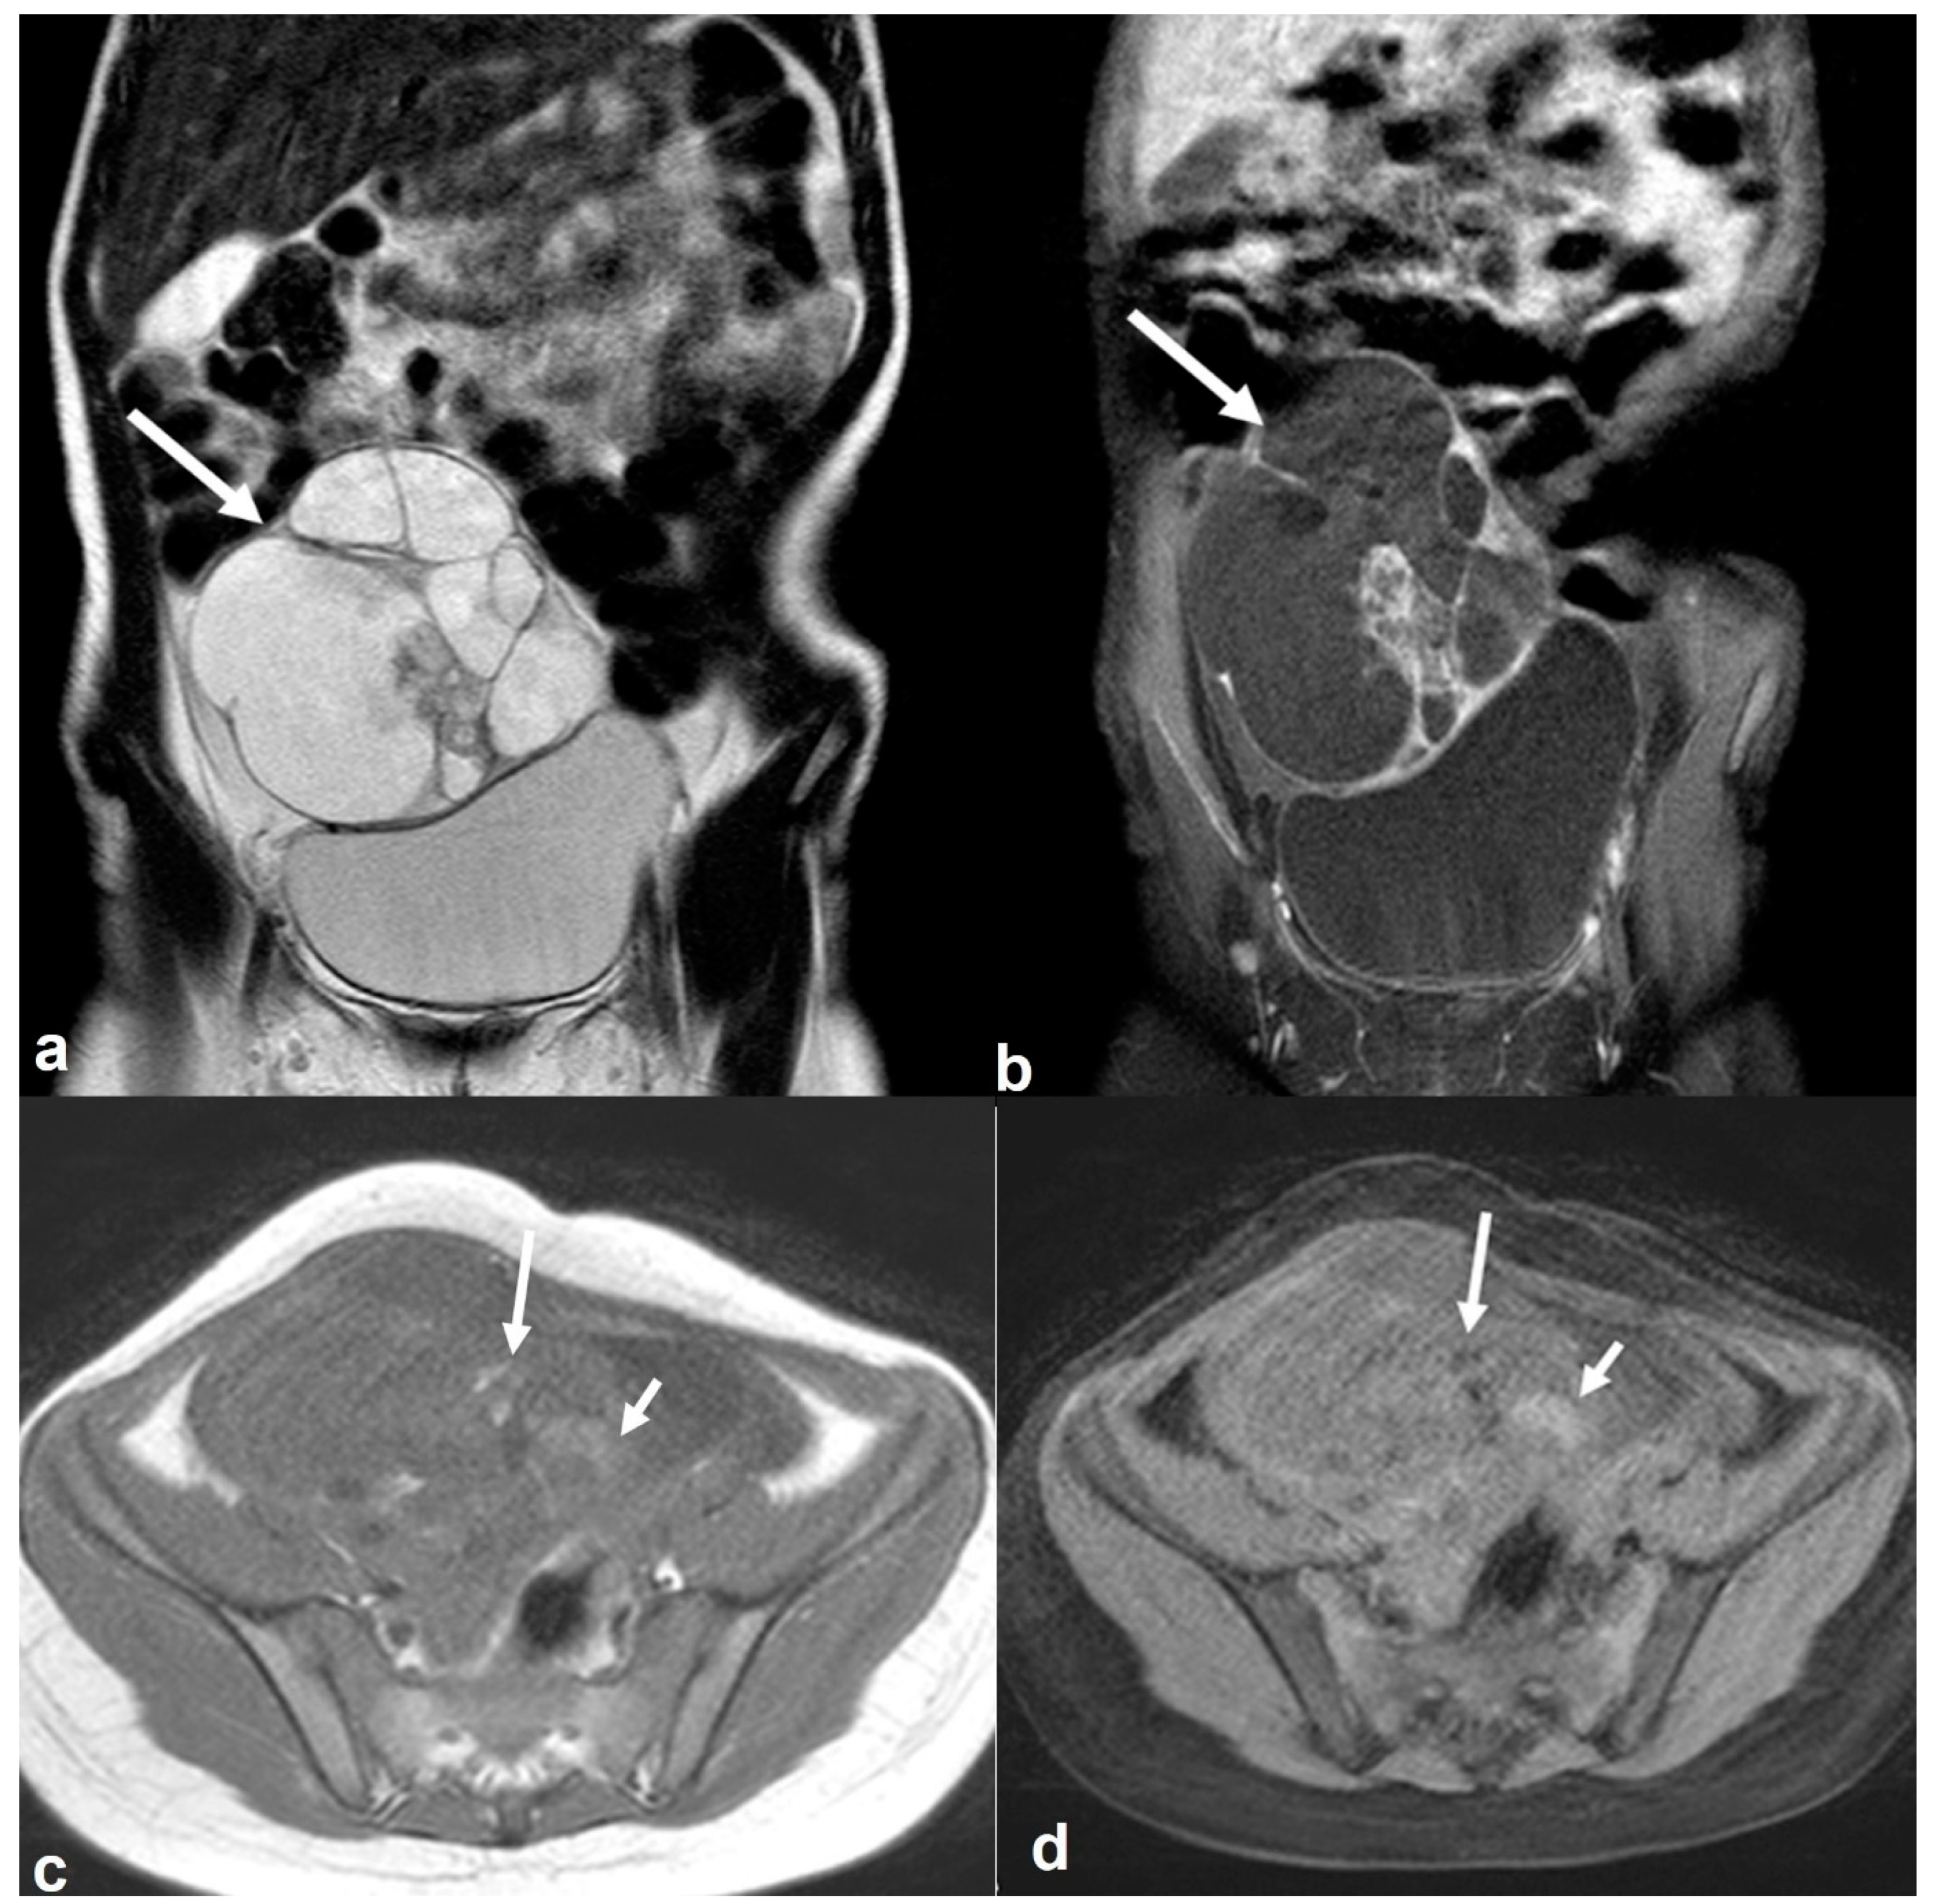

2.6.1. Mucinous Rectosigmoid Cancer

2.6.2. Appendiceal Mucocele—PMP